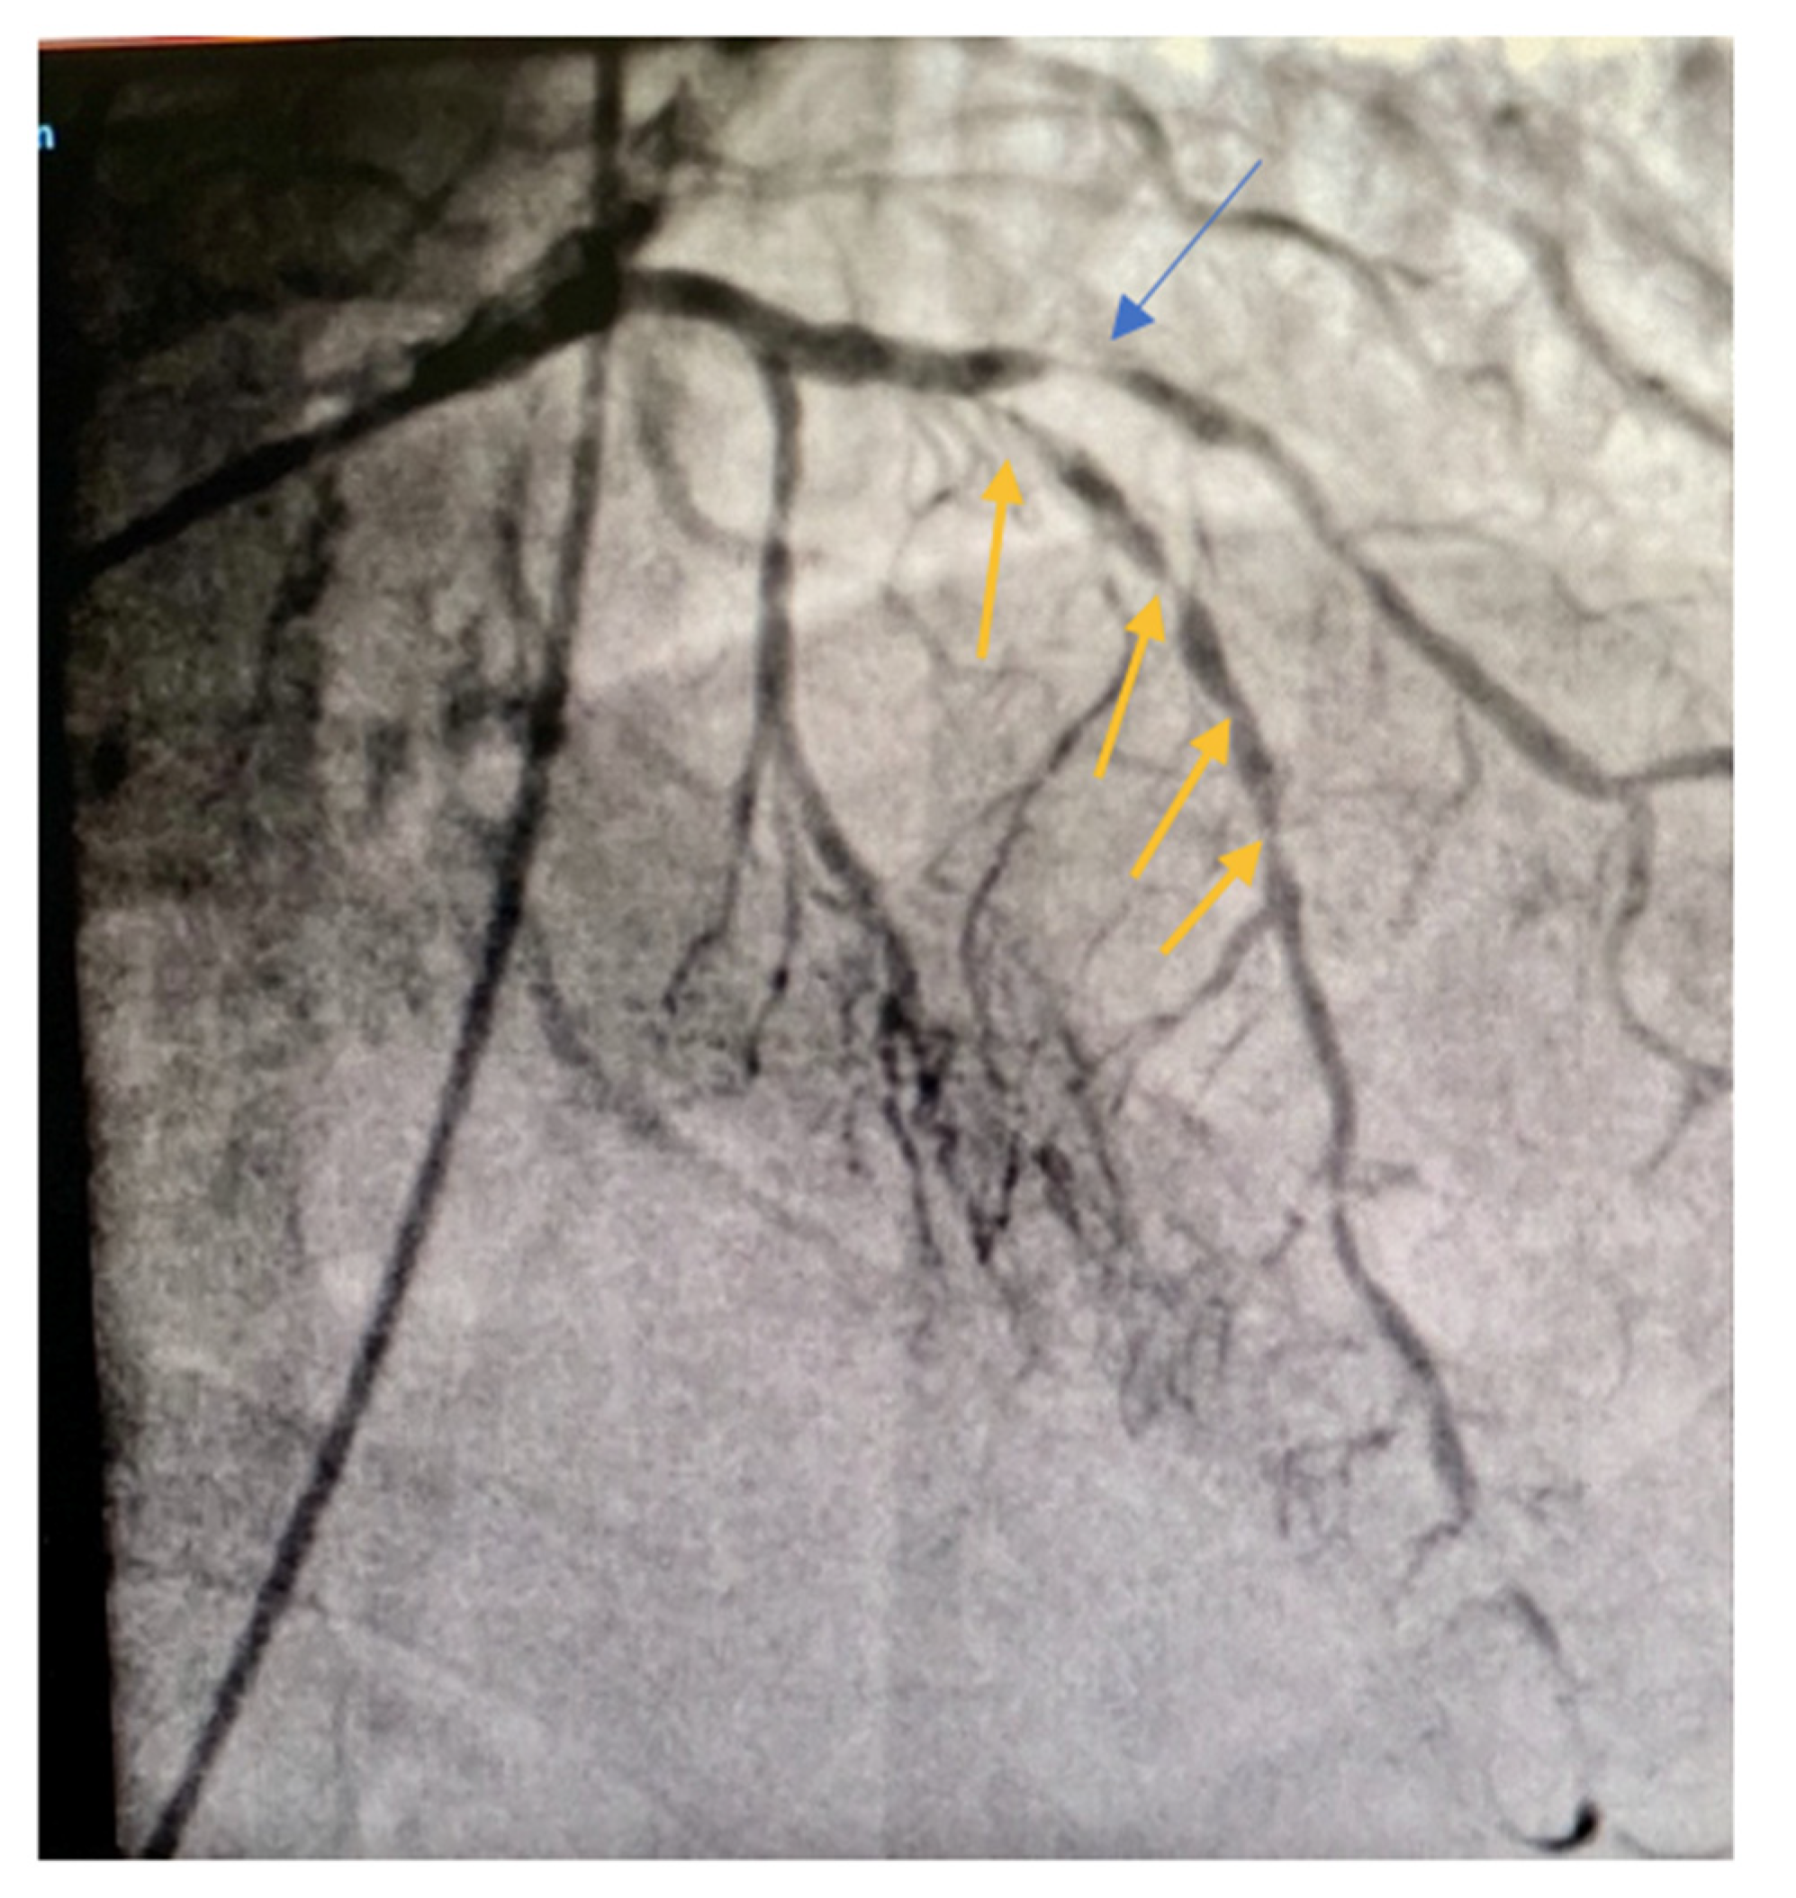

2. Case Report

Our Technique